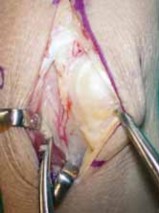

With the lunate prepared, the vascularized bone graft is harvested from the dorsal distal radius. We prefer the 4th/5th ECA pedicled graft. The 5th ECA is identified within the septum between the fourth and fifth extensor compartments. It is traced distally to its anastomosis with the 4th ECA. A bone block, typically measuring 10mm x 5mm x 5mm, is designed over the dorsal metaphysis of the radius, centered on the nutrient branches of the 4th ECA.

Using fine osteotomes, the cortical-cancellous bone block is carefully elevated. The pedicle is mobilized proximally, taking great care to separate it from the underlying posterior interosseous nerve (PIN). A cuff of periosteum and retinacular tissue is left attached to the bone block and pedicle to protect the delicate microscopic vessels. The tourniquet may be temporarily deflated at this stage to confirm pulsatile bleeding from the cancellous surface of the harvested bone block, ensuring graft viability.

Graft Inset and Final Fixation

The vascularized bone block is then gently rotated distally on its pedicle toward the lunate defect. The pedicle must not be twisted, kinked, or placed under any tension. If the lunate defect is larger than the vascularized